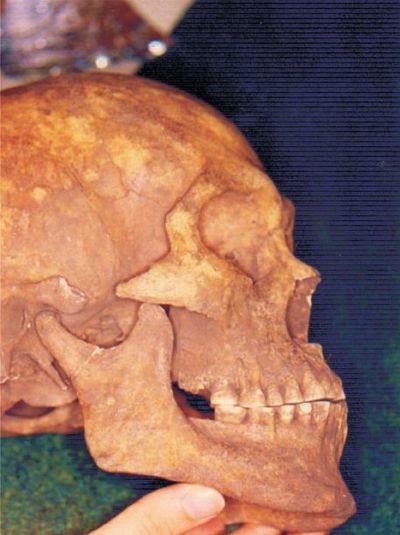

ARGUMENTOS BASADOS EN REFERENCIA A LA ANATOMÍA COMPARADA Y POBLACIONES ANTIGUAS.-

En cuanto a la aparición en poblaciones antiguas, es un punto sumamente importante y al cual cabe prestarle su debida atención (90).

Hasta donde hemos relevado se han descrito lesiones de tipo erosivas (80) pero no existen informaciones fidedignas que avalen la presencia de lesiones cervicales típicas para poblaciones prehistóricas, neolíticas, medievales (81) o con hábitos de “masticación primitivos” como australianos o esquimales (79, 82). Investigaciones en poblaciones prehistóricas del Uruguay tampoco las avalan, (tanto para poblaciones del este como del oeste y en numerosos yacimientos) (83, 84, 85).

En poblaciones rurales de Nigeria (84, 87) con masticación de dieta dura y fibrosa se encuentra atricción y desgaste oclusal pero sin lesiones cervicales correlacionables, las que sí se encuentran en poblaciones con hábitos modernos (88).

Por otro lado Brothwell (89) de minuciosos estudios sobre restos esqueletarios antiguos no ha descrito esta patología, detallando hallazgos de acanaladuras interproximales pero no muescas o cuñas cervicales.

Fig. 26, 27, 28 y 29. Investigación realizada con material esqueletario del Museo Nacional de Antropología proveniente de la zona conocida como "Cerritos de Rocha" (Uruguay). Comprende a individuos maduros que presentan reabsorción ósea y aumento de corona clínica. Se observa gran abrasión por masticación primitiva y atricción con contactos fuera de áreas no funcionales, (¿Bruxismo, Thegosis?). Fuerzas friccionales importantes que desarrollaron una fuerte musculatura y sólita arquitectura ósea. Balanceo bilateral. El individuo de la fig 29 presenta un marcado y asimétrico desgaste incisivo compatible con la utilización de la dentadura como herramienta. No hay presencia del LCNC.